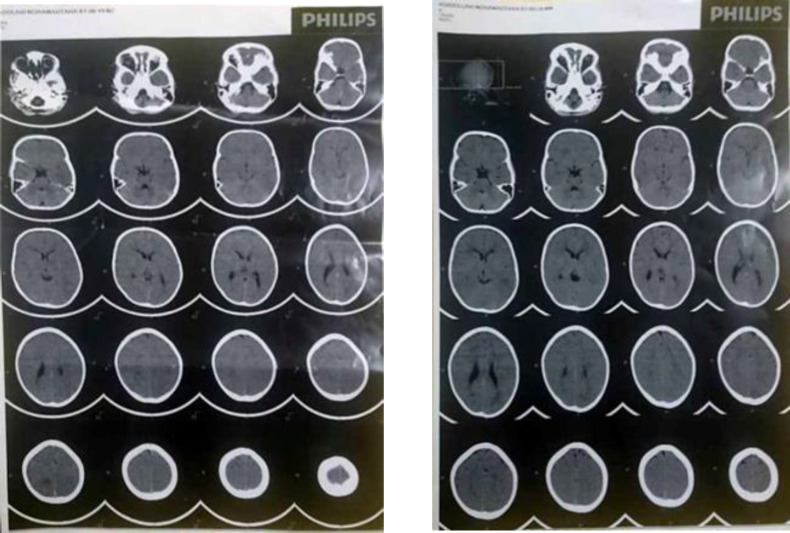

Case presentation: A 3 1/2-year-old boy presented with hemiplegia since the day before admission. Durig hospital admission, he experienced episodes of status epilepticus and loss of consciousness and underwent mechanical ventilation. The patient had silvery-gray hair, consequently the pathologic evaluation of the hair shaft, revealed enlarged irregularly spaced melanin clumps characteristic for silvery-gray hair syndrome. No immunologic dysfunction was detected due to immunological evaluations, subsequently Elejalde syndrome was confirmed.